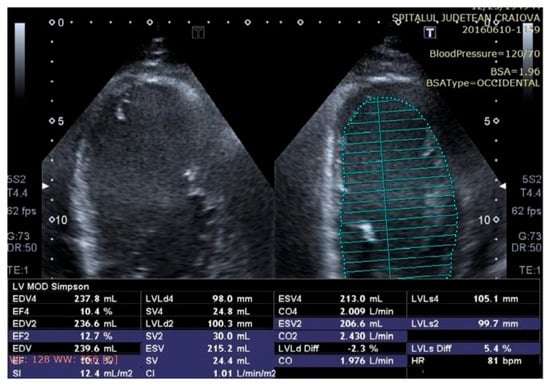

Some echocardiographic aspects revealed in the transthoracic echocardiographic examination before and after CRT are presented in Figure 3, Figure 4, Figure 5, Figure 6, Figure 7, Figure 8 and Figure 9.

Figure 4.

Two-dimensional echocardiography revealed a severely impaired left ventricular (LV) function with a low LV ejection fraction (LVEF) of 10% assessed according to the modified Simpson method, before therapy with a cardiac resynchronization device.

Figure 5.

Two-dimensional echocardiography revealed an improvement in left ventricular (LV) function with a low LV ejection fraction (LVEF) of 25% assessed according to the modified Simpson method, after therapy with a cardiac resynchronization device.